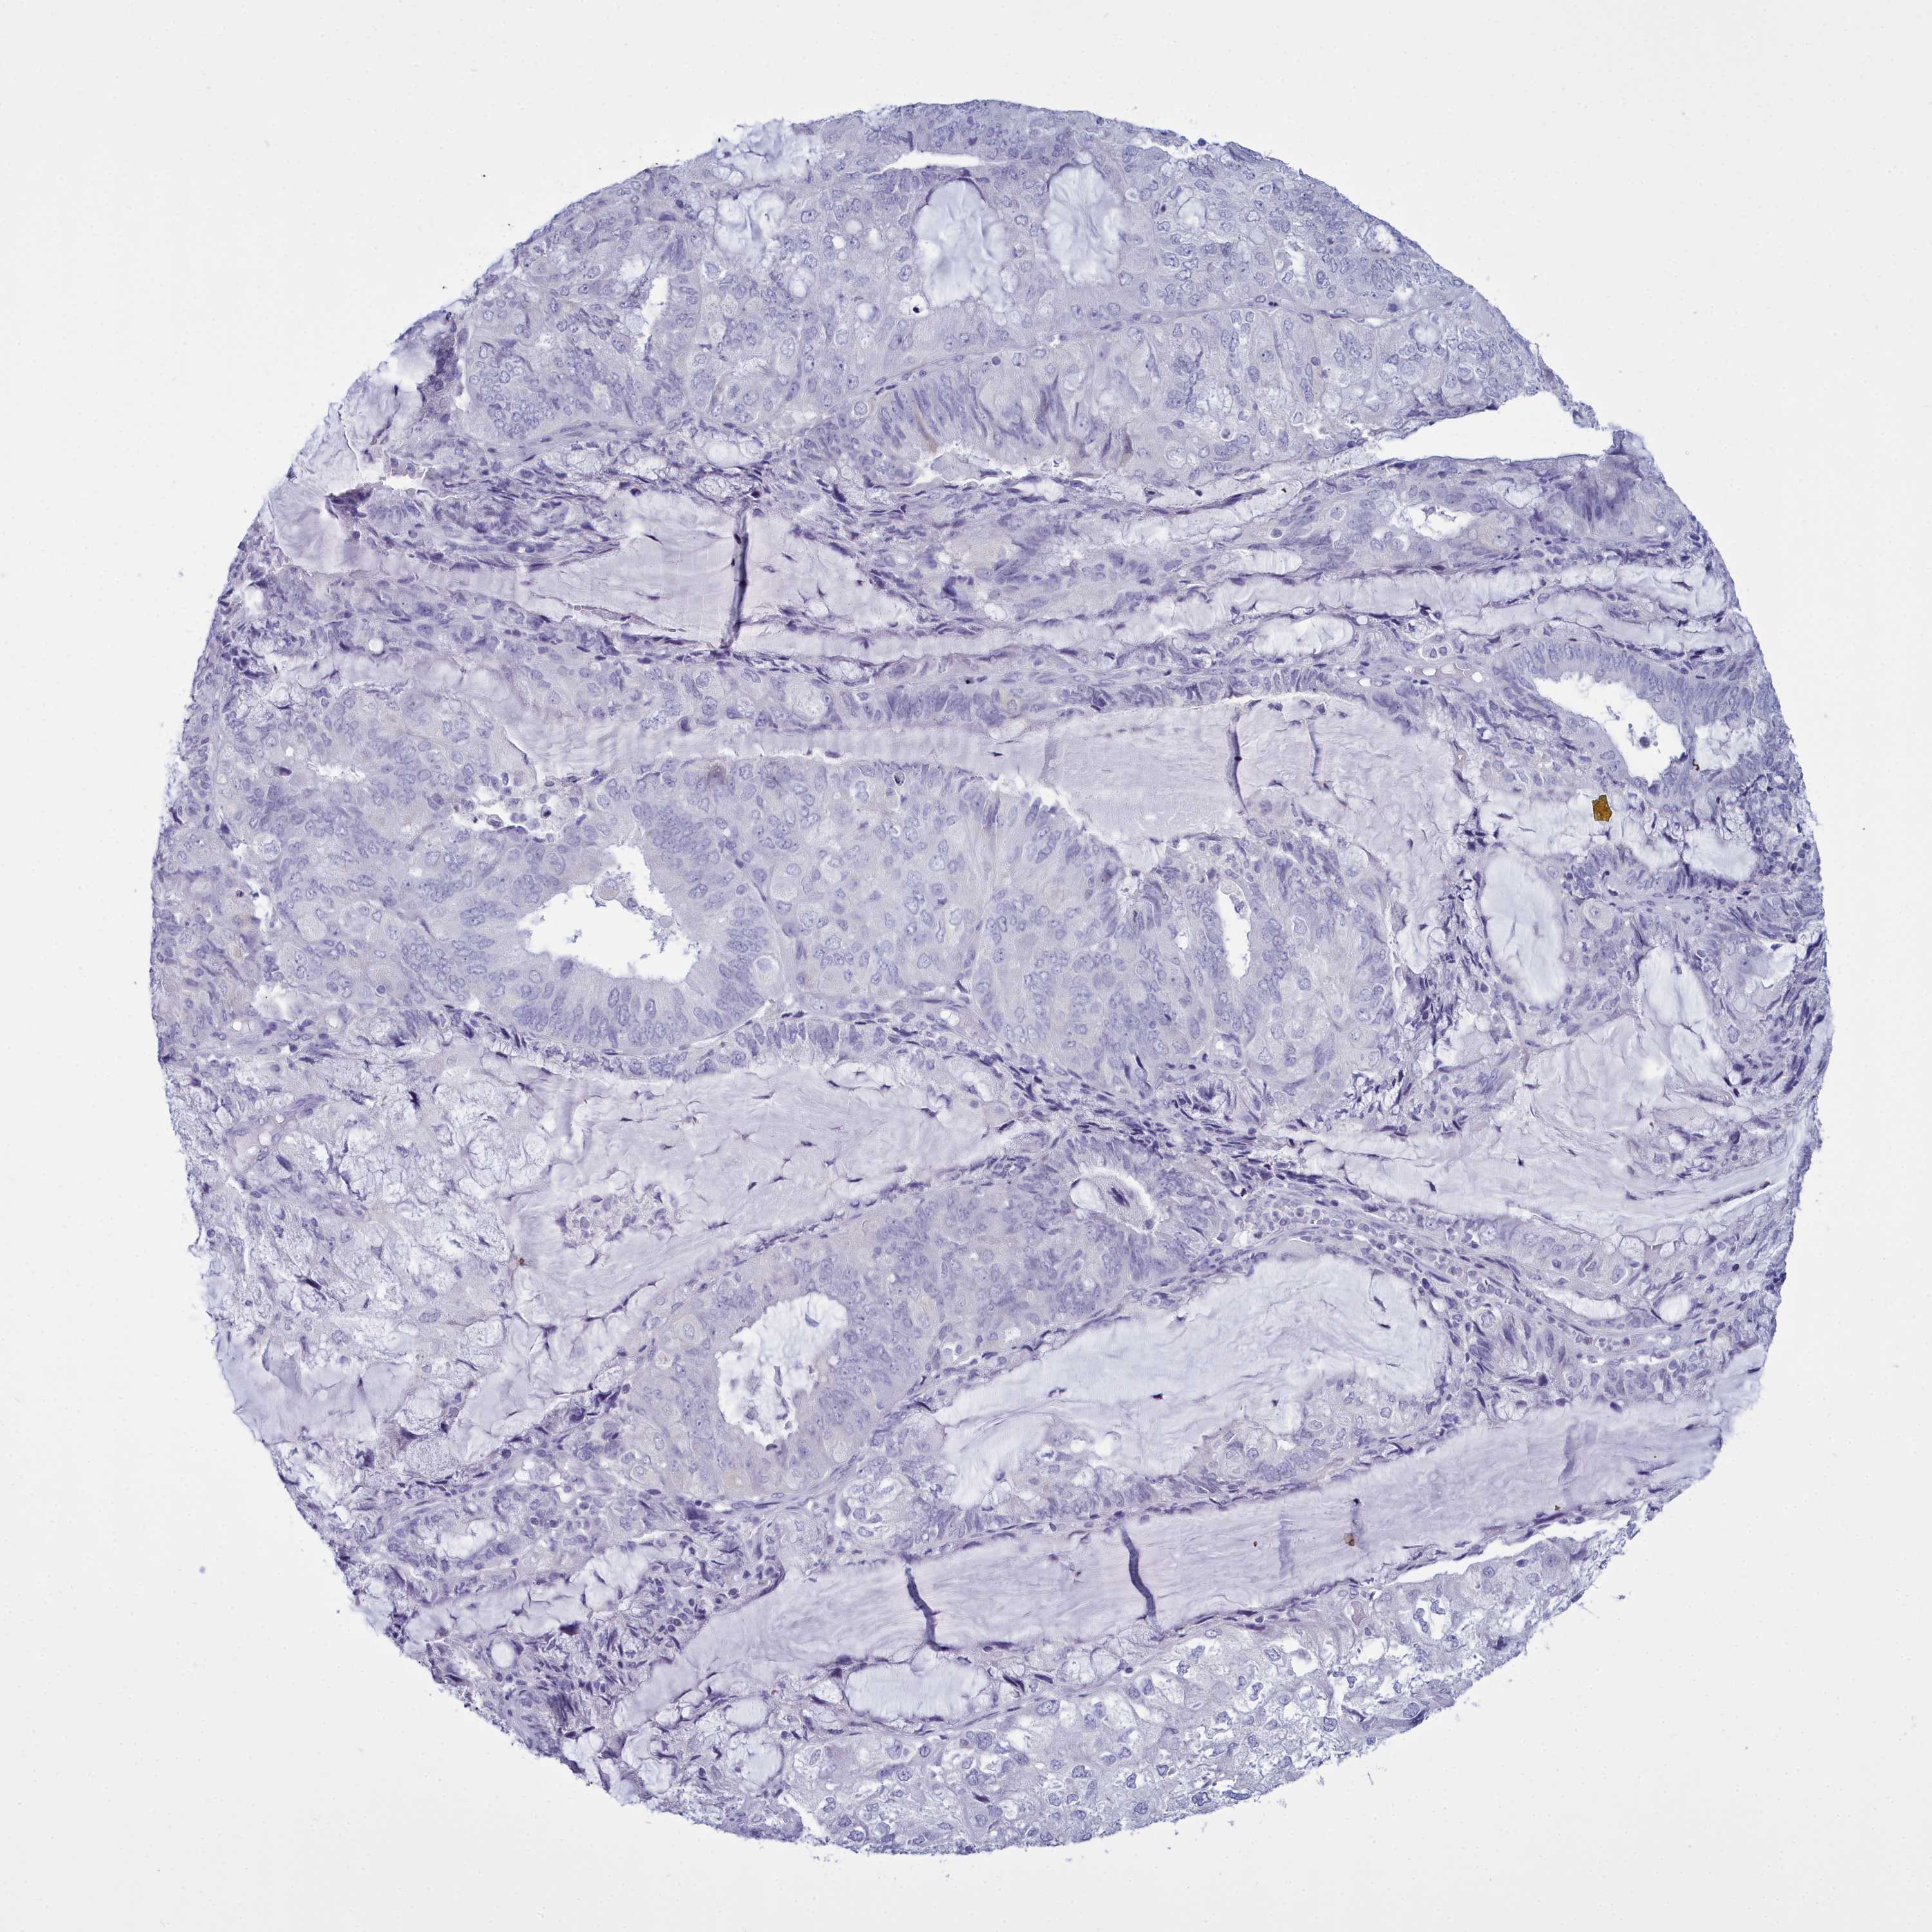

ENDOMETRIAL CANCER - Protein expressioni

A mouse-over function shows sample information and annotation data. Click on an image to view it in a full screen mode. Samples can be filtered based on level of antibody staining by selecting one or several of the following categories: high, medium, low and not detected. The assay and annotation is described here.

Note that samples used for immunohistochemistry by the Human Protein Atlas do not correspond to samples in the TCGA dataset.

Antibody stainingi

Antibody staining in the annotated cell types in the current human tissue is reported as not detected, low, medium, or high, based on conventional immunohistochemistry profiling in selected tissues. This score is based on the combination of the staining intensity and fraction of stained cells.

Each image is clickable and will lead to virtual microscopy that enables deeper exploration of all samples and also displays staining intensity scores, fraction scores and subcellular localization as well as patient and tissue information for each sample.

Antibody HPA039061

Antibody HPA039062

Antibody CAB015442

Antibody CAB022600

Staining

High

Medium

Low

Not detected

Intensity

Strong

Moderate

Weak

Negative

Quantity

>75%

75%-25%

<25%

None

Location

Nuclear

Cytoplasmic/membranous

Cytoplasmic/membranous,nuclear

Adenocarcinoma, NOS